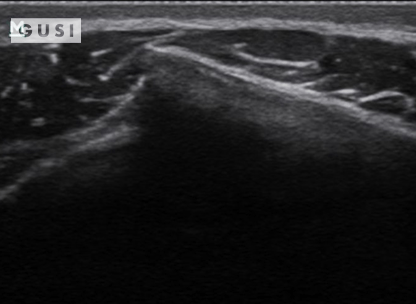

A 25-year-old male Taekwondo competitor from Africa experienced significant pain and tenderness in his right flank after receiving a forceful kick during the 2017 World Taekwondo Championships held in Muju, Korea. An immediate POCUS at the venue indicated a fracture in his 8th rib on the right anterior side of his chest.

A B

A: The rib showed angular displacement in the longitudinal view.

B: In the transverse view, the rib appeared displaced.

C: Subsequent chest ultrasound scans did not detect a pneumothorax, and the athlete had no breathing difficulties with stable vital signs.

Initial on-site management was conservative, and the athlete later sought additional treatment from his sports doctor back home. His team’s physiotherapist confirmed the fracture through an x-ray during a subsequent check-up. He fully recovered in a few weeks without facing any setbacks.